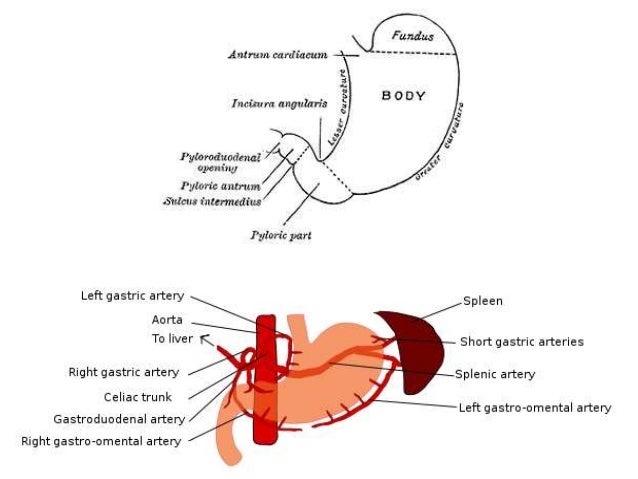

Thick tortuous folds or lobulated filling defects in the cardia or fundus. Right gastroepiploic artery inferiorly and left gastroepiploic artery and short gastric arteries superiorly fundus of the stomach. Results of surgical treatment of carcinoma of the esophagus and gastric cardia. The collection of cases presented here comprises only that material which is rare in our experience or quite new to us.

Cain jc jordan gl jr comfort mw gray hk. J am med assoc. The gas tric fundus is dened as the portion of the stomach craniad to the gastric car dia. Commonly accompanying this are abnormally dilated short gastric veins which pass from the splenic vein to encircle the gastric fundus and form gastric fundal varices.